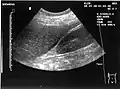

The hepatorenal recess[1] (subhepatic recess, pouch of Morison or Morison's pouch) is the subhepatic space that separates the liver from the right kidney. As a potential space, the recess is not normally filled with fluid. However, fluid can collect here in circumstances where the abdomen fills with fluid, such as hemoperitoneum. This fluid may be seen on ultrasound or computed tomography (CT scan).

Since it is a potential space, the hepatorenal recess is not normally filled with fluid. However, this space becomes significant in conditions in which fluid collects within the abdomen (most commonly ascites and hemoperitoneum). The intraperitoneal fluid, be it blood, ascites, or dialysate, collects in this space and may be visualized, most commonly via ultrasound or computed tomography (CT) scanning. As little as 30 or 40 ml of fluid in the abdominal cavity may be visualized in this space.

Early visualization of fluid in the hepatorenal recess on FAST scan may be an indication for urgent laparotomy.[2]